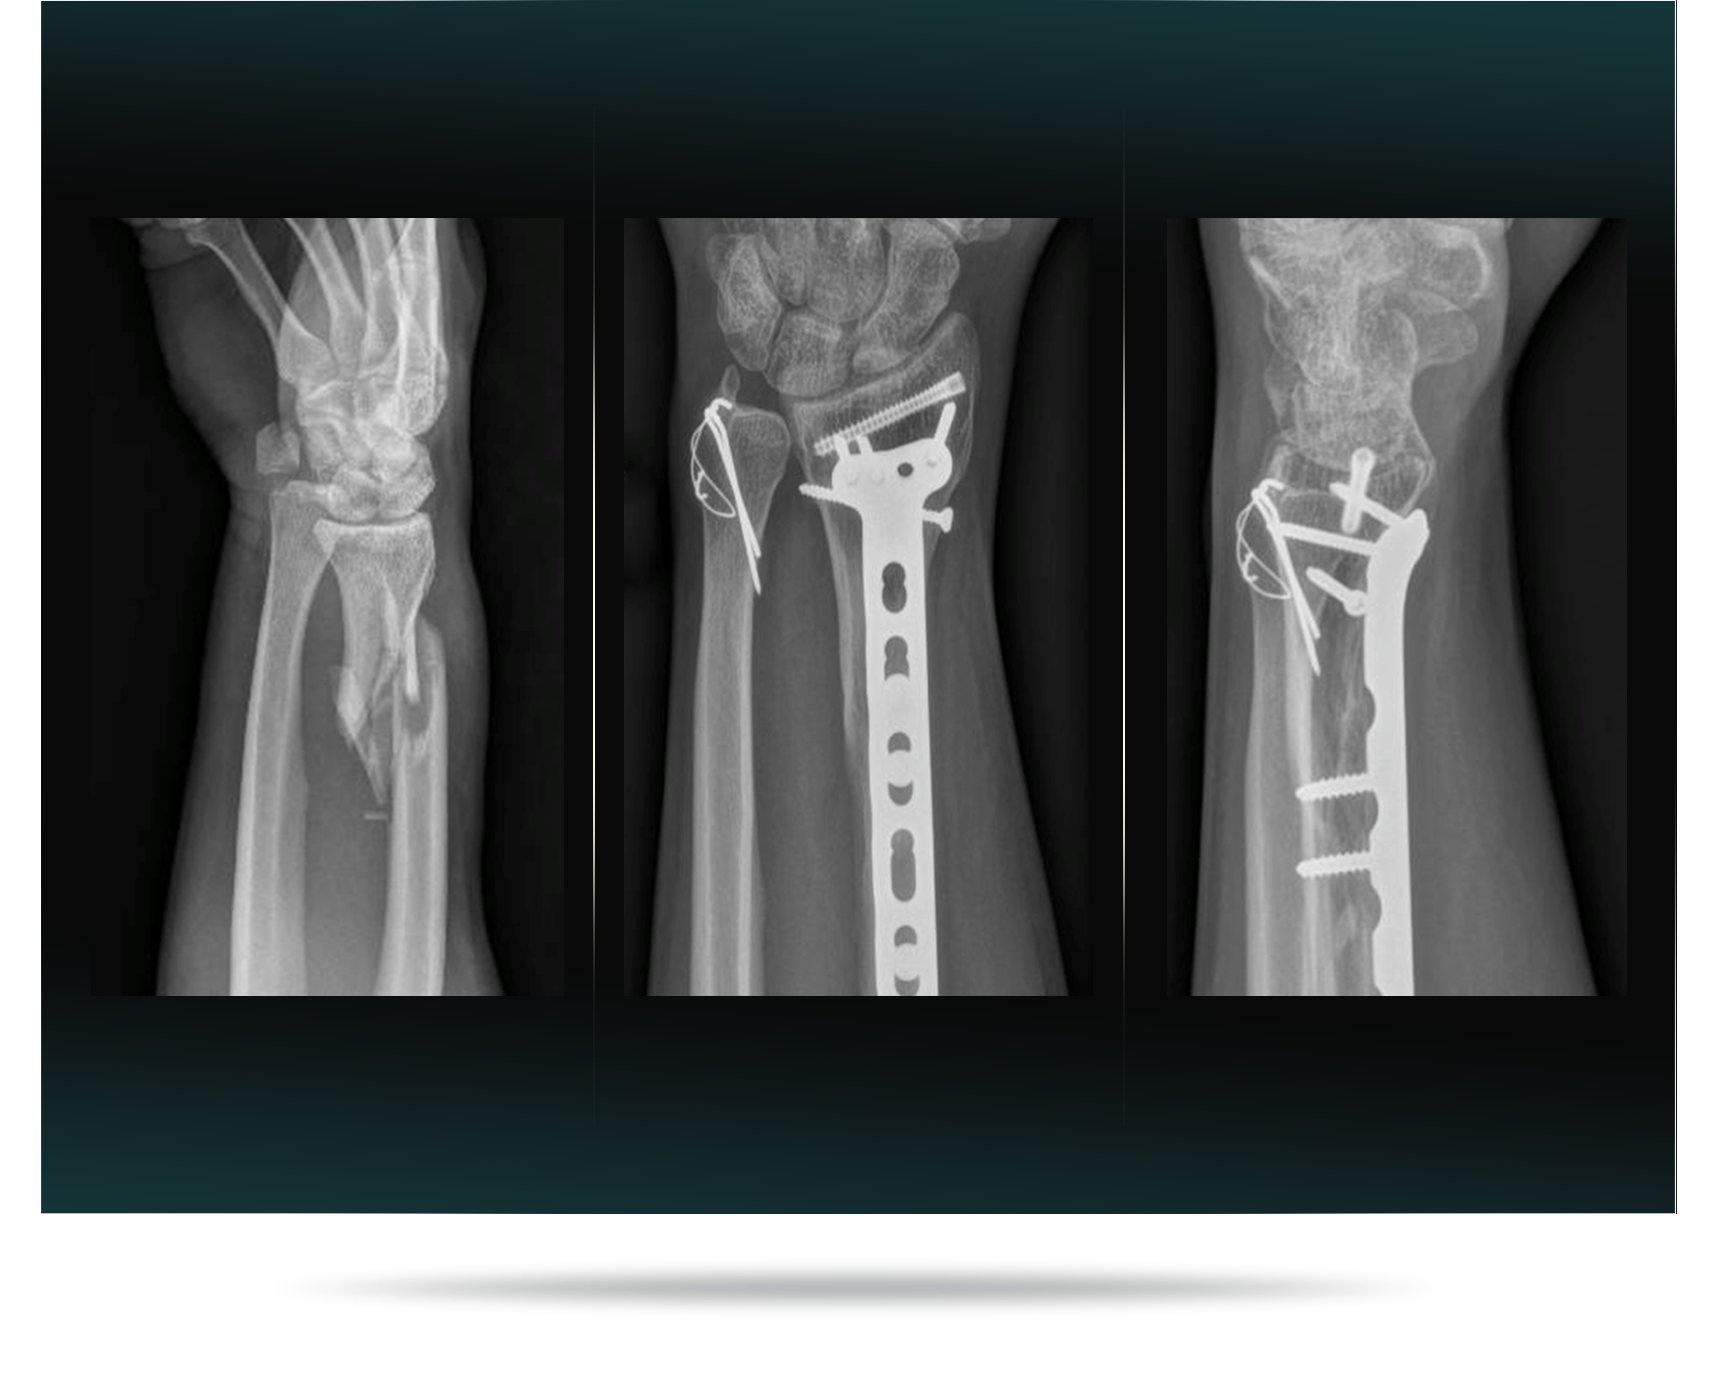

- Distal Radius Fractures (Broken Wrist)

- Wrist Fracture Treatment